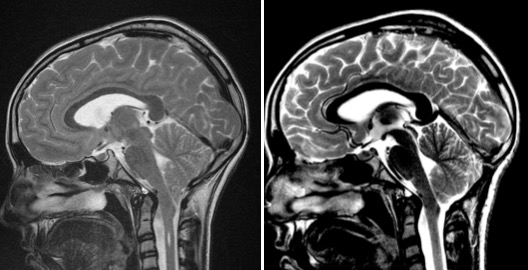

la « malformation de Chiari » est en fait un engagement tonsillaire chronique avec compression de la jonction bulbo-médullaire ; cet engagement peut s’auto-aggraver du fait de la pulsatilité cérébrale (« cork in the bottle« ). c’est un processus plus qu’un état, un phénomène avant tout hydrodynamique.

- que les critères radiologiques soient clairs :

- tonsilles effilées

- déformation de la jonction bulbo-médullaire

- surtout hypersignal T2 intra-axial